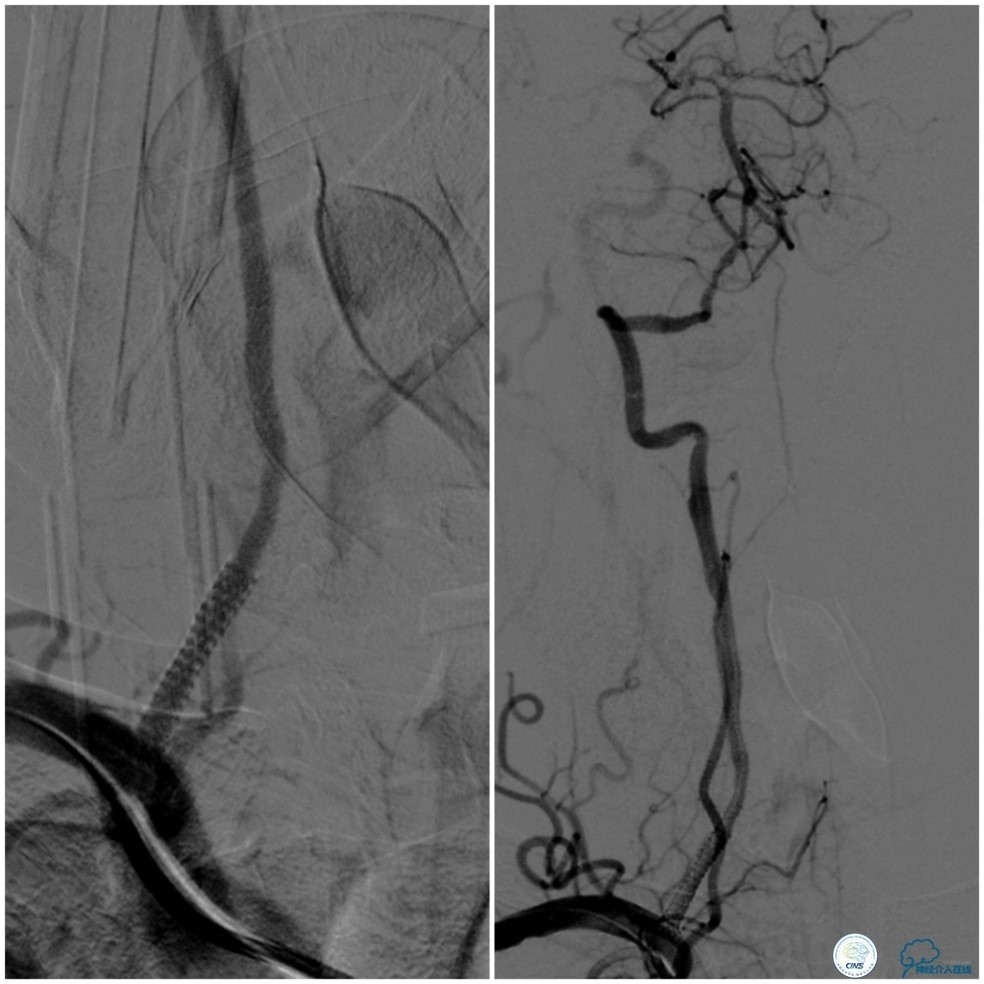

全麻下右侧股动脉穿刺置入8F动脉鞘,6F导引导管到位,送入Traxcess(0.014″200cm)微导丝+Echelon-10微导管谨慎通过右侧椎动脉V1段狭窄处至V2段远端,交换撤出Traxcess微导丝,送入Transend(0.014″300cm)微导丝至V2段远端(图10)。

图10

Ultra-Soft球囊(3.0mm×20mm)于狭窄处预扩张后置入EXCEL支架(4.0 mm× 24mm),球扩后造影见支架贴壁良好,远端血管显影好,前向血流TICI3级。6F导引导管沿微导丝通过右椎动脉V1段支架至V2段(图11)。

图11

此时多体外投照显示右椎V4-基底动脉极重度狭窄,几近闭塞(图12)。

图12

缓慢回撤6F导引导管至锁骨下动脉,造影显示右椎V1段支架无移位,前向血流正常(图17)。

图17